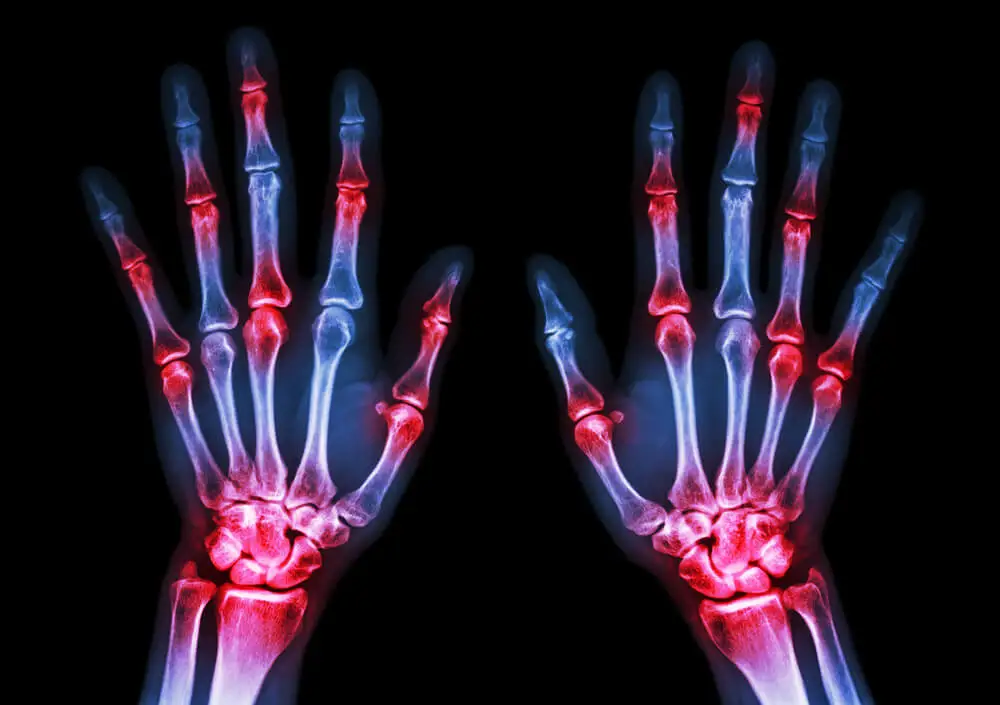

- O grau de maturação óssea deve apresentar um atraso. Para isso, são realizados exames complementares de imagem para medir a densidade dos ossos e sua conformação interna.

Por um lado, existe a possibilidade de atraso na puberdade. Isso afeta o desenvolvimento ósseo e torna os pacientes mais propensos a fraturas e lesões.